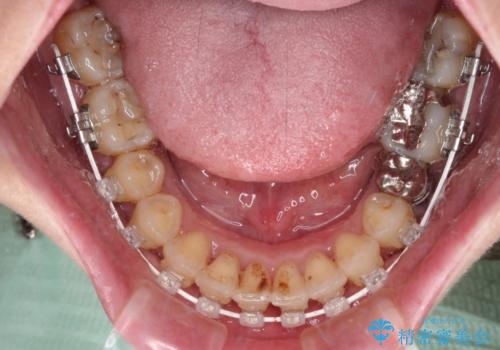

下顎前歯の叢生も気になっており、矯正治療も並行して進めていくこととしました。

- 治療中は歯磨きがしにくくなるため、虫歯や歯周病になりやすくなります